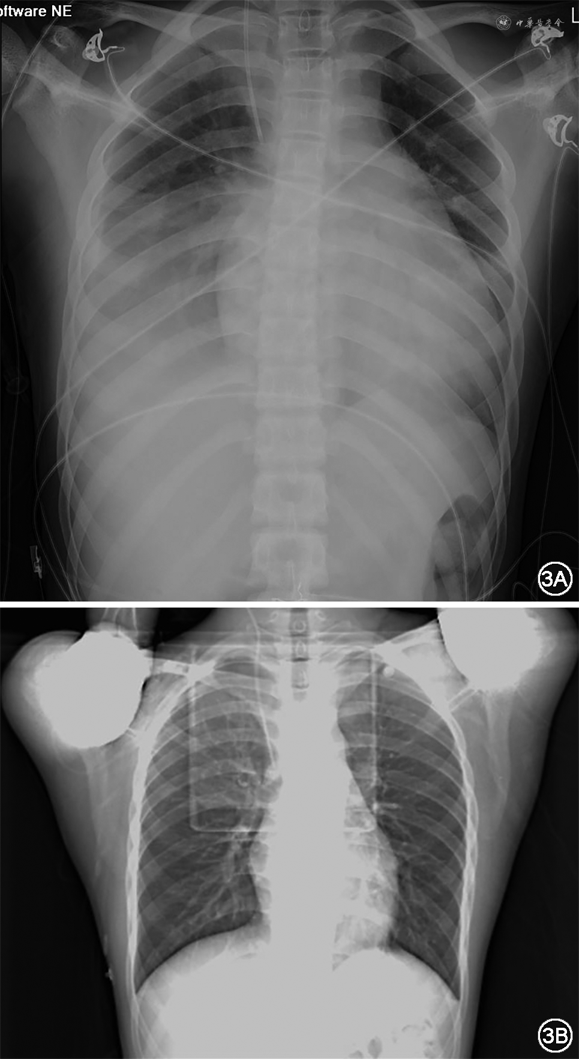

住院第2天(11月26日)超声心动图示:左心房前后径(left atrial diameter,LAD)39 mm,左心室舒张末期内径(left ventricular end-diastolic diameter,LVEDD)55 mm,左心室射血分数(left ventricular ejection fraction,LVEF)39%。超声心动图结论:符合心肌受累疾患超声改变,全心增大伴二三尖瓣少量返流,轻度肺动脉高压,少量心包积液(图2A)。床旁胸片提示:全心增大伴双侧胸腔积液(图3A)。26日上午室速再发,心室率130次/分,在静脉基础上加用口服维拉帕米80 mg,3次/d。夜间出现频发室性期前收缩(室早),R on T,随即演变为室颤(图1C和图4),患者抽搐,电除颤1次转为窦性心律,仍见频发R on T室早,后以利多卡因50 mg静脉注射,后以4 mg/min静脉泵入,室早明显减少;即刻查血钾3.84 mmol/L,血钠133 mmol/L,血镁0.99 mmol/L。当天查心电图提示:QTc=541 ms(心率78次/分)。

住院第10天(12月4日)安排患者出院,出院时心电图(图1D):QTc=483 ms(心率49次/分)。复查胸片(图3B)提示:双侧胸腔积液消失,心影明显回缩。复查床旁超声心动图示:LVEDD 47 mm,LVEF 49%。NT-proBNP 154.8pg/mL。